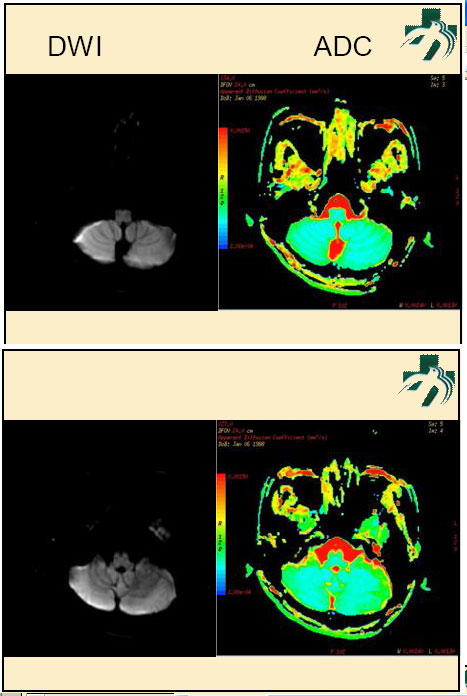

奴卡氏菌感染

第九期三博

读片会

病例之四

北京协和医院 提供

男性,22岁。自觉虫咬后皮疹、肢体麻木4月